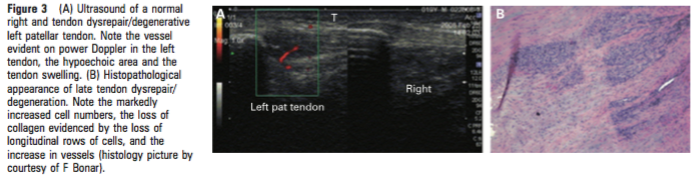

Quid de l’imagerie  (figure 2 et 3) ?

L’examen qui permet à ce jour de quantifier le plus précisément ce continuum est l’échographie. L’échographie permet de visualiser la structure du tendon et la présence de zones plus ou moins hypoechogènes, de quantifier son épaisseur, et grâce au doppler puissance, elle permet de déterminer la présence ou non de petits vaisseaux sanguins caractéristiques de la phase de remaniement avancée ou de la phase dégénérative.

Source : Cook et al 2009